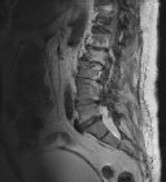

Figures 1 and 2 show sagittal and axial MRI from an 83-year-old woman with an ataxic gait, loss of dexterity, and intermittent loss of bowel and bladder control. The symptoms have been getting progressively worse over the past several weeks.

What disease process is most likely the cause of the patient’s symptoms?

4. Pigmented villonodular synovitis Discussion: B

The patient has a pannus at the C1-2 articulation that is compressing the spinal cord and causing myelopathy symptoms. The development of a pannus at this location has been associated with rheumatoid arthritis. Steinberger and associates showed increased morbidity and mortality when using an anterior approach and the surgery took longer than 4 hours. Chieng and associates showed better outcomes and lower complications rates using a posterior approach.

CLINICAL SITUATION

When discussing anterior versus posterior surgical techniques, you counsel this patient that

Discussion: A